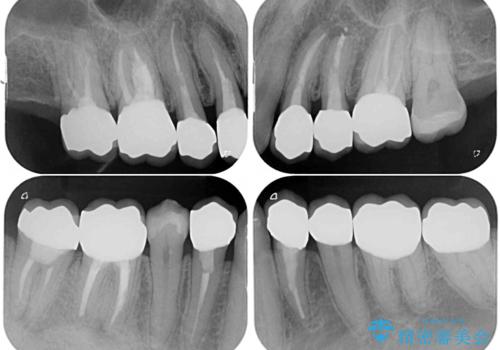

矯正治療後には、奥歯の銀歯をすべてセラミックにて補綴治療することとしました。

補綴治療にあたり、痛みのある歯に対して根管治療を行うこととしましたが、処置が必要な歯が多かったため、期間を要しました。

補綴治療中に前歯のデコボコが戻ってしまったため、補綴治療後にインビザラインを1セット追加して仕上げました。